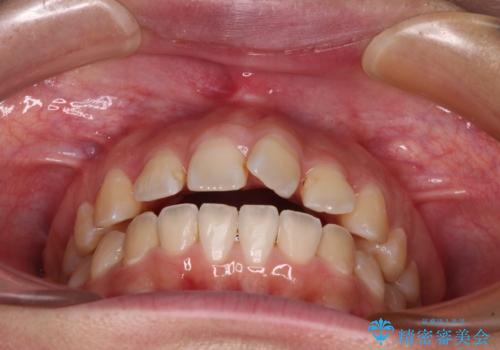

- 上下の前歯が非接触であることと、それに伴う口元の閉じにくさを気にして来院された患者様です。

奥歯の咬み合わせを見ると、上顎が下顎に対して相対的に前方にありました。

口元の閉じにくさを改善するためには、上顎臼歯を後方に移動させた咬み合わせにする必要があります。

インビザライン単体で改善することも可能ですが、達成する可能性が高くないため、カリエールディスタライザーという補助装置を併用して、より確実性を上げることとしました。

奥歯の咬み合わせを改善しながら、並行してインビザラインで歯列を整えることとしました。

カリエールディスタライザーを併用したことで、確実かつ短期間で治療を終えることができました。